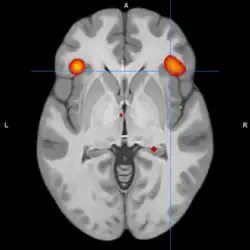

Neuroimaging and postmortem studies have identified abnormalities in several brain regions, with the ventral prefrontal cortex and amygdala being most frequently implicated. Dysfunction within the emotional circuits of these regions has been hypothesized as a potential mechanism underlying bipolar disorder.[2] Additionally, evidence points to abnormalities in neurotransmission, intracellular signaling, and cellular functioning as contributing factors.[3]

A model of functional neuroanatomy produced by a workgroup led by Stephen M. Strakowski concluded that bipolar was characterized by reduced connectivity, due to abnormal pruning or development, in the prefrontal-striatal-pallidal-thalamic-limbic network leading to dysregulated emotional responses. This model was supported by a number of common neuroimaging findings. Dysregulation of limbic structures is evinced by the fact that hyperactivity in the amygdala in response to facial stimuli has been consistently reported in mania.[33] While amygdala hyperactivity is not a uniform finding, a number of methodological challenges could explain discrepancies. As most studies utilize fMRI to measure blood-oxygen-level dependent signal, excess baseline activity could result in null findings due to subtraction analysis. Furthermore, heterogenous study design could mask consistent hyperactivity to specific stimuli. Regardless of directionality of amygdala abnormalities, as the amygdala plays a central role in emotional systems, these findings support dysfunctional emotional circuits in bipolar. A general reduction in ventrolateral prefrontal cortex activity is observed in bipolar, and is lateralized with regard to mood (i.e., left-depression, right-mania), and may underlie amygdala abnormalities. The dorsal ACC is commonly under-activated in bipolar, and is generally implicated in cognitive functions, while the ventral ACC is hyperactive and implicated in emotional functions. Combined, these abnormalities support the prefrontal-striatal-pallidial-thalamic limbic network underlying dysfunction in emotional regulation in bipolar disorder.[34] Strakowski, along with DelBello and Adler have put forward a model of "anterior limbic" dysfunction in bipolar disorder in a number of papers.[35][36][37][38][39]

Blond et al. proposed a model centered on dysfunction in an "amygdala-anterior paralimbic" system. This model was based on the consistent functional and structural abnormalities in the ventral prefrontal cortex and amygdala. The model also proposes a developmental component of bipolar disorder, wherein limbic abnormalities are present early on, but rostral prefrontal abnormalities develop later in the course. The importance of limbic dysfunction early in development is highlighted by the observation that amygdala lesions early in adulthood produce emotional abnormalities that are not present in people who develop amygdala damage in adulthood.[41]

During cognitive or emotional tasks, functional neuroimaging studies, consistently find hyperactivation of the basal ganglia, amygdala, and thalamus. Prefrontal abnormalities are less consistently reported, although hyperactivation in the ventral prefrontal cortex is a fairly consistent finding.[72] Hyperactivity in the amygdala and hypoactivity in the medial and ventral prefrontal cortex during exposure to emotional stimuli has been interpreted as reflecting dysfunction in emotional regulation circuits. Increased effective connectivity between the amygdala and orbitofrontal cortex, and elevated striatal responsiveness during reward tasks have been interpreted as hyper-responsiveness in positive emotion and reward circuitry. The abnormal activity in these circuits has been observed in non-emotional tasks, and is congruent with changes in grey and white matter in these circuits.[73] Neural response during reward tasks differentiates unipolar depression from bipolar depression, with the former being associated with reduced neural response and the latter being associated with elevated neural response.[74] An ALE meta analysis of functional neuroimaging comparing adults and adolescents found a larger degree of hyperactivity in the inferior frontal gyrus and precuneus, as well as a larger degree of hypoactivity in the anterior cingulate cortex in adolescents relative to adults[75]